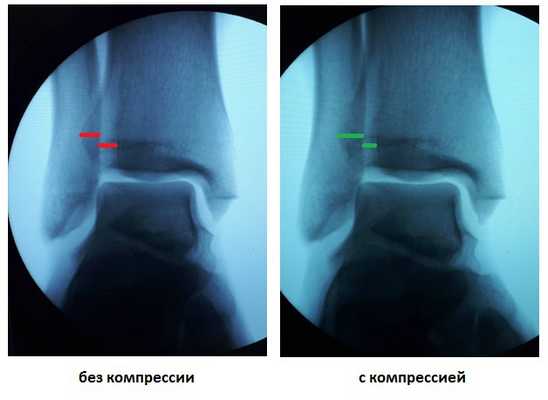

При выполнении стресс рентгенограмм определяется выраженная латеральная нестабильность голеностопного сустава.

У данного пациента также определялась избыточная подвижность малоберцовой кости на уровне дистального межберцового синдесмоза при компрессии голени на уровне средней трети, которая клинически проявляется болью по переднему краю наружной лодыжки.